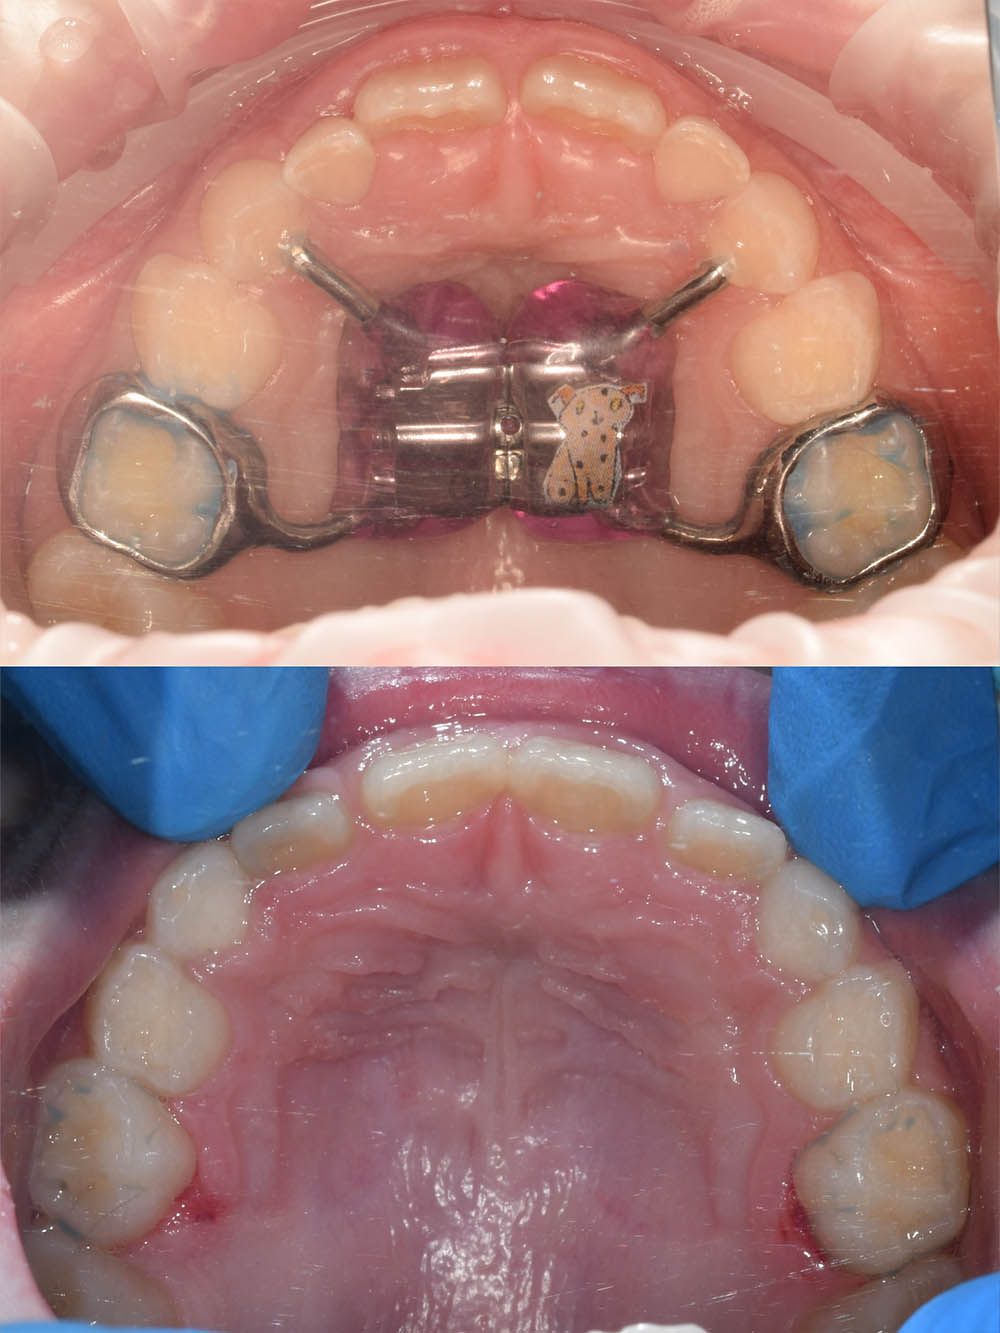

Лечение ребёнка на частичной брекет-системе

Лечение ребёнка на частичной брекет-системе

Лечение ребёнка на частичной брекет-системе

Лечение ребёнка на частичной брекет-системе